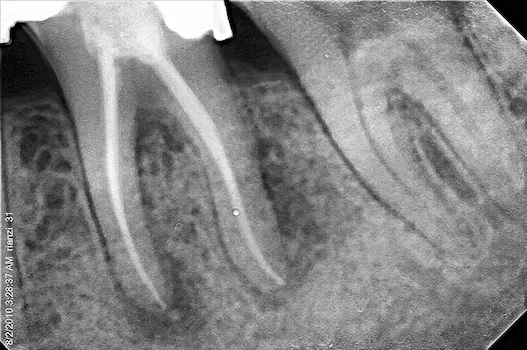

A Root Canal Treatment is conducted by a Root Canal Specialist, Also known as an Endodontist when a patient comes in with a decayed or damaged tooth that might be infected. It is advisable to go through with the procedure rather than extracting the tooth as retaining natural teeth is always better than getting a false one after an extraction and not replacing teeth after extraction can affect the health of the remaining teeth. The soft inner chamber of the tooth known as the pulp –contains Nerves, Blood vessels and Connective tissue. When the pulp gets damaged or infected due to a chip in the tooth or dental decay that allows bacteria to enter, A Root Canal procedure needs to be performed in order to remove the infected pulp and clean and seal the inside of the tooth.

The duration of a Root Canal Procedure varies depending upon the severity of infection. Some Root Canal Treatment can be completed in a single sitting and are known as Single Visit Root Canal Treatment however, If the tooth is badly infected it might involve multiple sittings as your Endodontist has to ensure that all the infection has healed prior to filling the tooth.